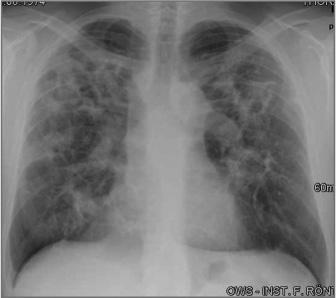

Der Radiologische Befund ist eine der klinischen Kriterien um die Tuberkulose zu diagnostizieren. Prof. Dr Gerhard Mostbeck betont gerade deshalb die Wichtigkeit, die gesamten radiologischen Möglichkeiten in der Diagnostik der Tuberkulose auszuschöpfen. Denn die Tuberkulose weist je nach Immunlage unterschiedlich Ausprägungsmöglichkeiten auf, kann alle Organsysteme befallen und simuliert viele andere Erkrankungen. In Abhängigkeit, ob es sich um eine Miliartuberkulose, Primärtuberkulose oder postprimäre Form handelt, können unterschiedliche charakteristische Veränderungen in der Bildgebung in Erscheinung treten. Das Lungenröntgen stellt den Grundpfeiler dar, auf dem sich die weiteren diagnostischen Methoden wie Sonographie, CT und MRT stützen und je nach Ausprägung und Organbefall eine exaktere Zuordnung zulassen. Professor Mostbecks Vortrag gibt einen praktischen Überblick über den richtigen und zielführenden Einsatz der bildgebenden Verfahren, um damit dem großen „Mimiker Tuberkulose“ auf die Schliche zu kommen.